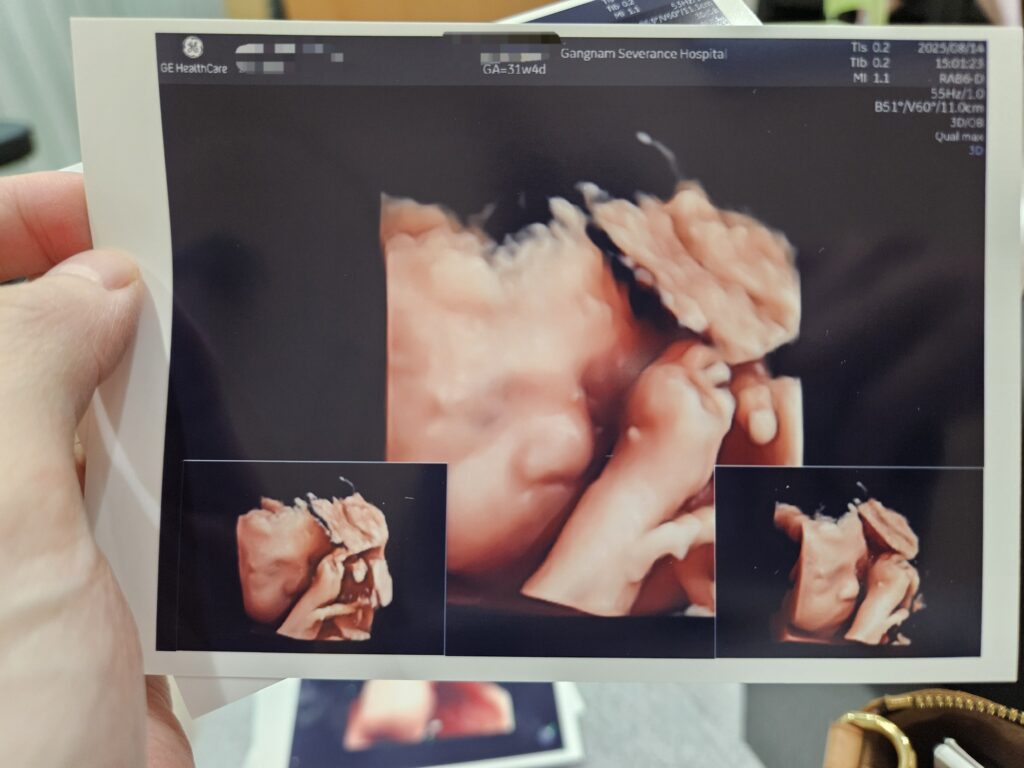

여튼,, 단비의 입초를 한 번 더 볼 수 있어서 너무 좋았다. 입초 단비는 내 아기라서 그런지 몰라도 너무너무 귀엽다.

초진이라 진료 상황이 어떻게 될 지 몰라서 일단 오빠에게 오지 말라고 했는데, 정밀초음파랑 입체초음파를 받을 줄 알았더라면 오빠도 데리고 왔을 것이다. 그냥 같이 와달라고 할 걸 후회했다.

진료가 끝나고 아기 측정 수치를 받아보고 싶다고 해서, 아래 사진을 추가로 받았다.

단비 AC (배둘레)는 99%가 넘어간다. OVER.. ㄷㄷㄷ

그리고 단비 소뇌 관련 수치(Cereb, CM)가 큰 몸집에 비해 작게 나와서 조금 걱정되었다.

다만 강남세브란스의 초음파 기계가 구식인 것 같고 여러 모로 못 미더워서, 소뇌에 대해서는 아무래도 봄빛병원의 신식 기계로 한번 더 측정을 한 후 의견을 들어봐야겠다는 생각이 들었다.